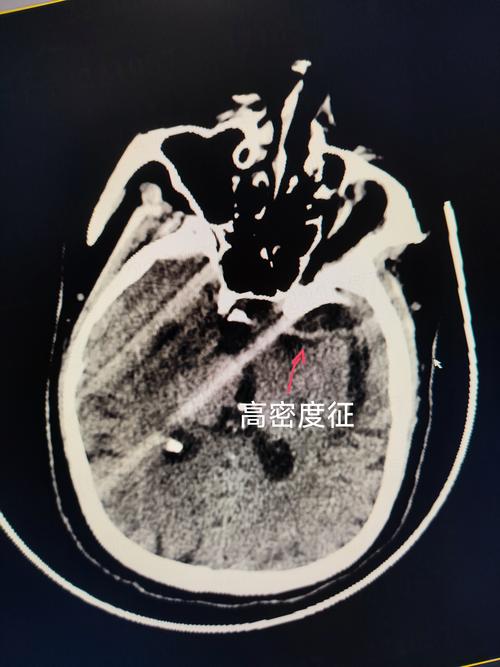

(图片来源网络,侵删)

C. 左侧移位 (Shifted to the Left)

- 通俗理解:原本在正中央的“中线结构”,现在被推向了左边。

- 深层含义:这说明右侧大脑的压力,比左侧大脑的压力要大得多,就像一个气球,如果一边被用力挤压,中间的隔膜就会被推向另一侧。

- 中线被挤压:右侧巨大的压力,像推土机一样,把位于正中央的“中线结构”(大脑镰等)硬生生地推向了压力较小的左侧。